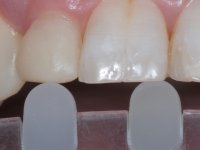

Treatment began with re-preparation of the cast post and core, with the purpose of placing the cervical finishing lines with an intra-sulcular location and simultaneously making a suitable temporary crown. With a very simple orthodontic treatment, the diastema was closed between the upper central incisors, and this position was stabilized with a wire placed on the palatal surface of the central, functioning as containment. Later, a slow orthodontic traction of tooth 2.2 was attempted, in order to reduce, although very slightly, the vertical bone loss in this area. At the end of the traction, tooth 2.2 was extracted and the area was provisionally rehabilitated with a composite resin crown bonded to the adjacent teeth. A dental implant was placed in the area of tooth 2.2 and the temporary crown was again bonded to resin, provisionally rehabilitating the patient during osseointegration. In tooth 1.3 a gingivectomy with an electric scalpel was performed, with the intention of raising the cervical level of 1.3 achieving greater harmony with tooth 2.3. Stabilized soft tissues were impressed using the open tray technique with putty and light addition silicones. Collection of the color of both the dental component and soft tissues was done by the ceramist in the office. In the laboratory, the impressions were transferred to plaster and gave origin to work models that were properly analyzed. It was decided to assemble a metal-ceramic abutment screwed onto the implant. This abutment was cast with a noble alloy and subsequently coated with coronary and gingival ceramics. Due to the inclination of the implant, the screwing inevitably conditioned the exit of the screw hole through the vestibular surface. In order to conceal this situation, the design of the abutment has already been conceived with the intention of accommodating on the vestibular surface the bonding of a feldspathic veneer. This abutment was tested in the mouth and adjustments were made in the gingival ceramic component. Its adaptation to the soft tissues was done in a subtractive way, with a drill, as well as additive, adding resin composed of gingival tonality.

This addition of resin would guide the ceramist in the final placement of the gingival tonality ceramic. The crown that would rehabilitate tooth 1.3 was cemented in this test session with glass ionomer cement, reinforced with composite resin. Once the laboratory work was finished on the veneer for tooth 1.2, the abutment, and the veneer for the implant, this was bonded in the mouth, after placement of the absolute insulation. The work completely satisfied the patient. For eight years, the patient had periodical check-ups, and was pleased with the treatment, but also began to show interest in an aesthetical intervention on the upper central incisors. Once the second phase of our intervention was decided, dental preparation of teeth 1.1 and 2.1 was performed for the placement of two feldspathic veneers. Particular care was taken in the distal inter-proximal preparation adjacent to the abutment of the implant.